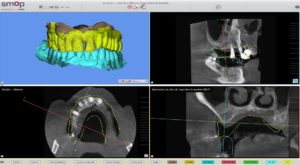

Un cone beam et une prise d’empreinte optique ont été nécessaire pour réaliser la planification implantaire du cas.

Un waxup esthétique haut et bas a aussi été réalisé.

Il a été prévu de poser 6 implants au Maxillaire et 4 implants à la mandibule .

2 guides SMOP ont été imprimé, appuis dentaires, muqueux + fixation par clavettes.